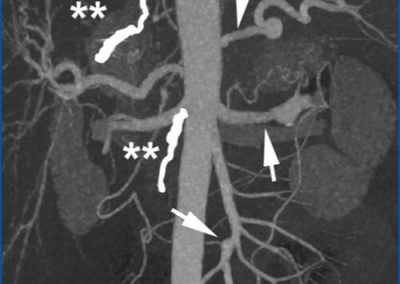

All images, protocols, and outcomes are courtesy of Dr. Richard Hallett, Banner University Medical Center – Phoenix, Phoenix, AZ.